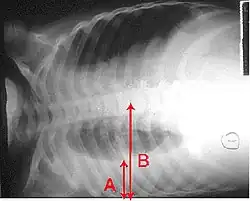

La neumonía se diagnostica con una combinación de la clínica que presenta el afectado, incluyendo tos, fiebre y dificultad respiratoria y confirmada por la consolidación pulmonar observable en una radiografía de tórax. La etiología se establece con cultivo bacteriológico del esputo y de la sangre (hemocultivo). A menudo una broncoscopia es indicada para ciertos pacientes hospitalizados.[9] El diagnóstico acertado puede ser difícil en pacientes con otras enfermedades. Ocasionalmente se emplea la tomografía y otros exámenes para diferenciar una neumonía de otras enfermedades, como el cáncer de pulmón.

Un examen importante para el diagnóstico acertado de una neumonía es la radiografía de tórax, que puede mostrar áreas de opacidad (vistas como zonas blanquecinas), que representan áreas de consolidación. La neumonía no siempre se puede apreciar en una radiografía de tórax, bien porque se trate de un estadio inicial de la enfermedad o porque se halle infectada una porción de los pulmones que no se observa en una radiografía. Una radiografía puede también ser difícil de interpretar en pacientes con fibrosis pulmonar e insuficiencia cardíaca congestiva.[11] En algunos casos se amerita realizar una tomografía computarizada.